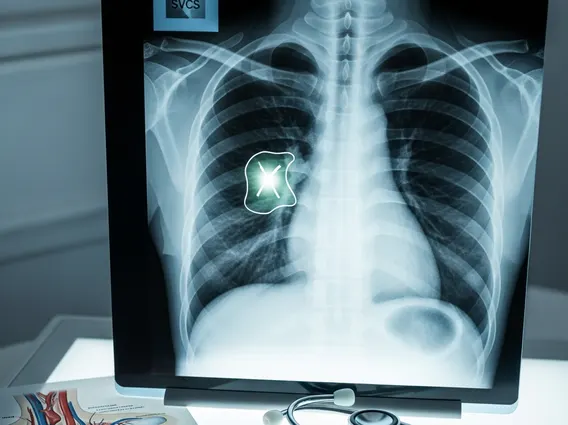

- Diagnosis involves imaging studies like CT scans to identify the obstruction.

- Radiation Therapy: This is a common treatment for malignant causes, particularly when the tumor is sensitive to radiation (e.g., small cell lung cancer, lymphoma). It aims to shrink the tumor and relieve compression on the SVC.

- Chemotherapy: Used for chemosensitive tumors, often in combination with radiation therapy. It can rapidly reduce tumor size and improve symptoms.

- Endovascular Stenting: A minimally invasive procedure where a stent is placed within the SVC to physically open the narrowed or blocked vessel. This provides rapid symptom relief and is often used in cases of severe or rapidly worsening symptoms, or when other treatments are not immediately effective.